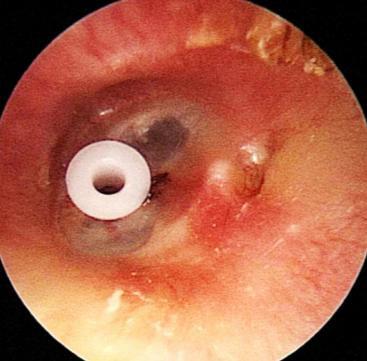

中耳通氣管置放手術後照護

中耳通氣管為置放在耳膜上, 建立一個中耳腔與外界交通 的人工通道;使中耳內的積水 能流出,並可代替人體原有 耳咽管之通氣功能。